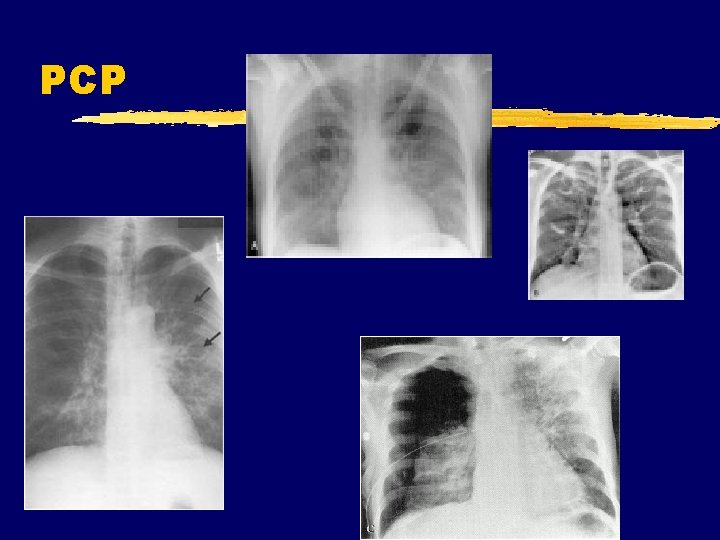

PCP

PCP z Symptoms y Incidious onset y SOB>cough y pneumothorax z Findings y diffuse infiltrates in a perihilar or bibasilar distribution and a reticular or reticulonodular pattern y No effusion y Elevated LDH y SX>>>CXR x. Normal in 26% z Diagnosis y. Sputum for DFA y. Sputum cytology y. BAL for same y. Histopathology/stains